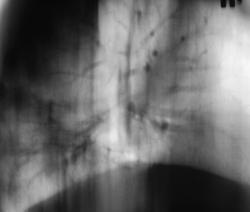

Возникло обоснованное сомнение в "полном клиническом выздоровлении". Решено сделать томографию в боковой проекции.

Визуально как периферическое образование, вы его на МСКТ направляли?

Нет, мы , по всей видимости, и не будем направлять его на МСКТ. Просто продолжим курс противововспалительной терии еще на 1 неделю, затем сделаем 5 срез, и уже из полученного будем решать.

Я соглашусь с Валентином Львовичем, частенько в онкодиспансер присылают пациентов с такой картиной. Они конечно не сразу добираются.А когда приезжают, делаем контроль, а там не к чему прицепиться.